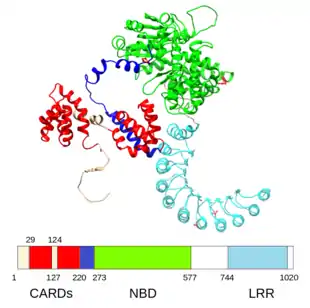

The first mutation found to be associated with Crohn's was a frameshift in the NOD2 gene (also known as the CARD15 gene),[73] followed by the discovery of point mutations.[74] Over 30 genes have been associated with Crohn's; a biological function is known for most of them. For example, one association is with mutations in the XBP1 gene, which is involved in the unfolded protein response pathway of the endoplasmic reticulum.[75][76] The gene variants of NOD2/CARD15 seem to be related with small-bowel involvement.[77] Other well documented genes which increase the risk of developing Crohn disease are ATG16L1,[78] IL23R,[79] IRGM,[80] and SLC11A1.[81] There is considerable overlap between susceptibility loci for IBD and mycobacterial infections.[82] Genome-wide association studies have shown that Crohn's disease is genetically linked to coeliac disease.[83]